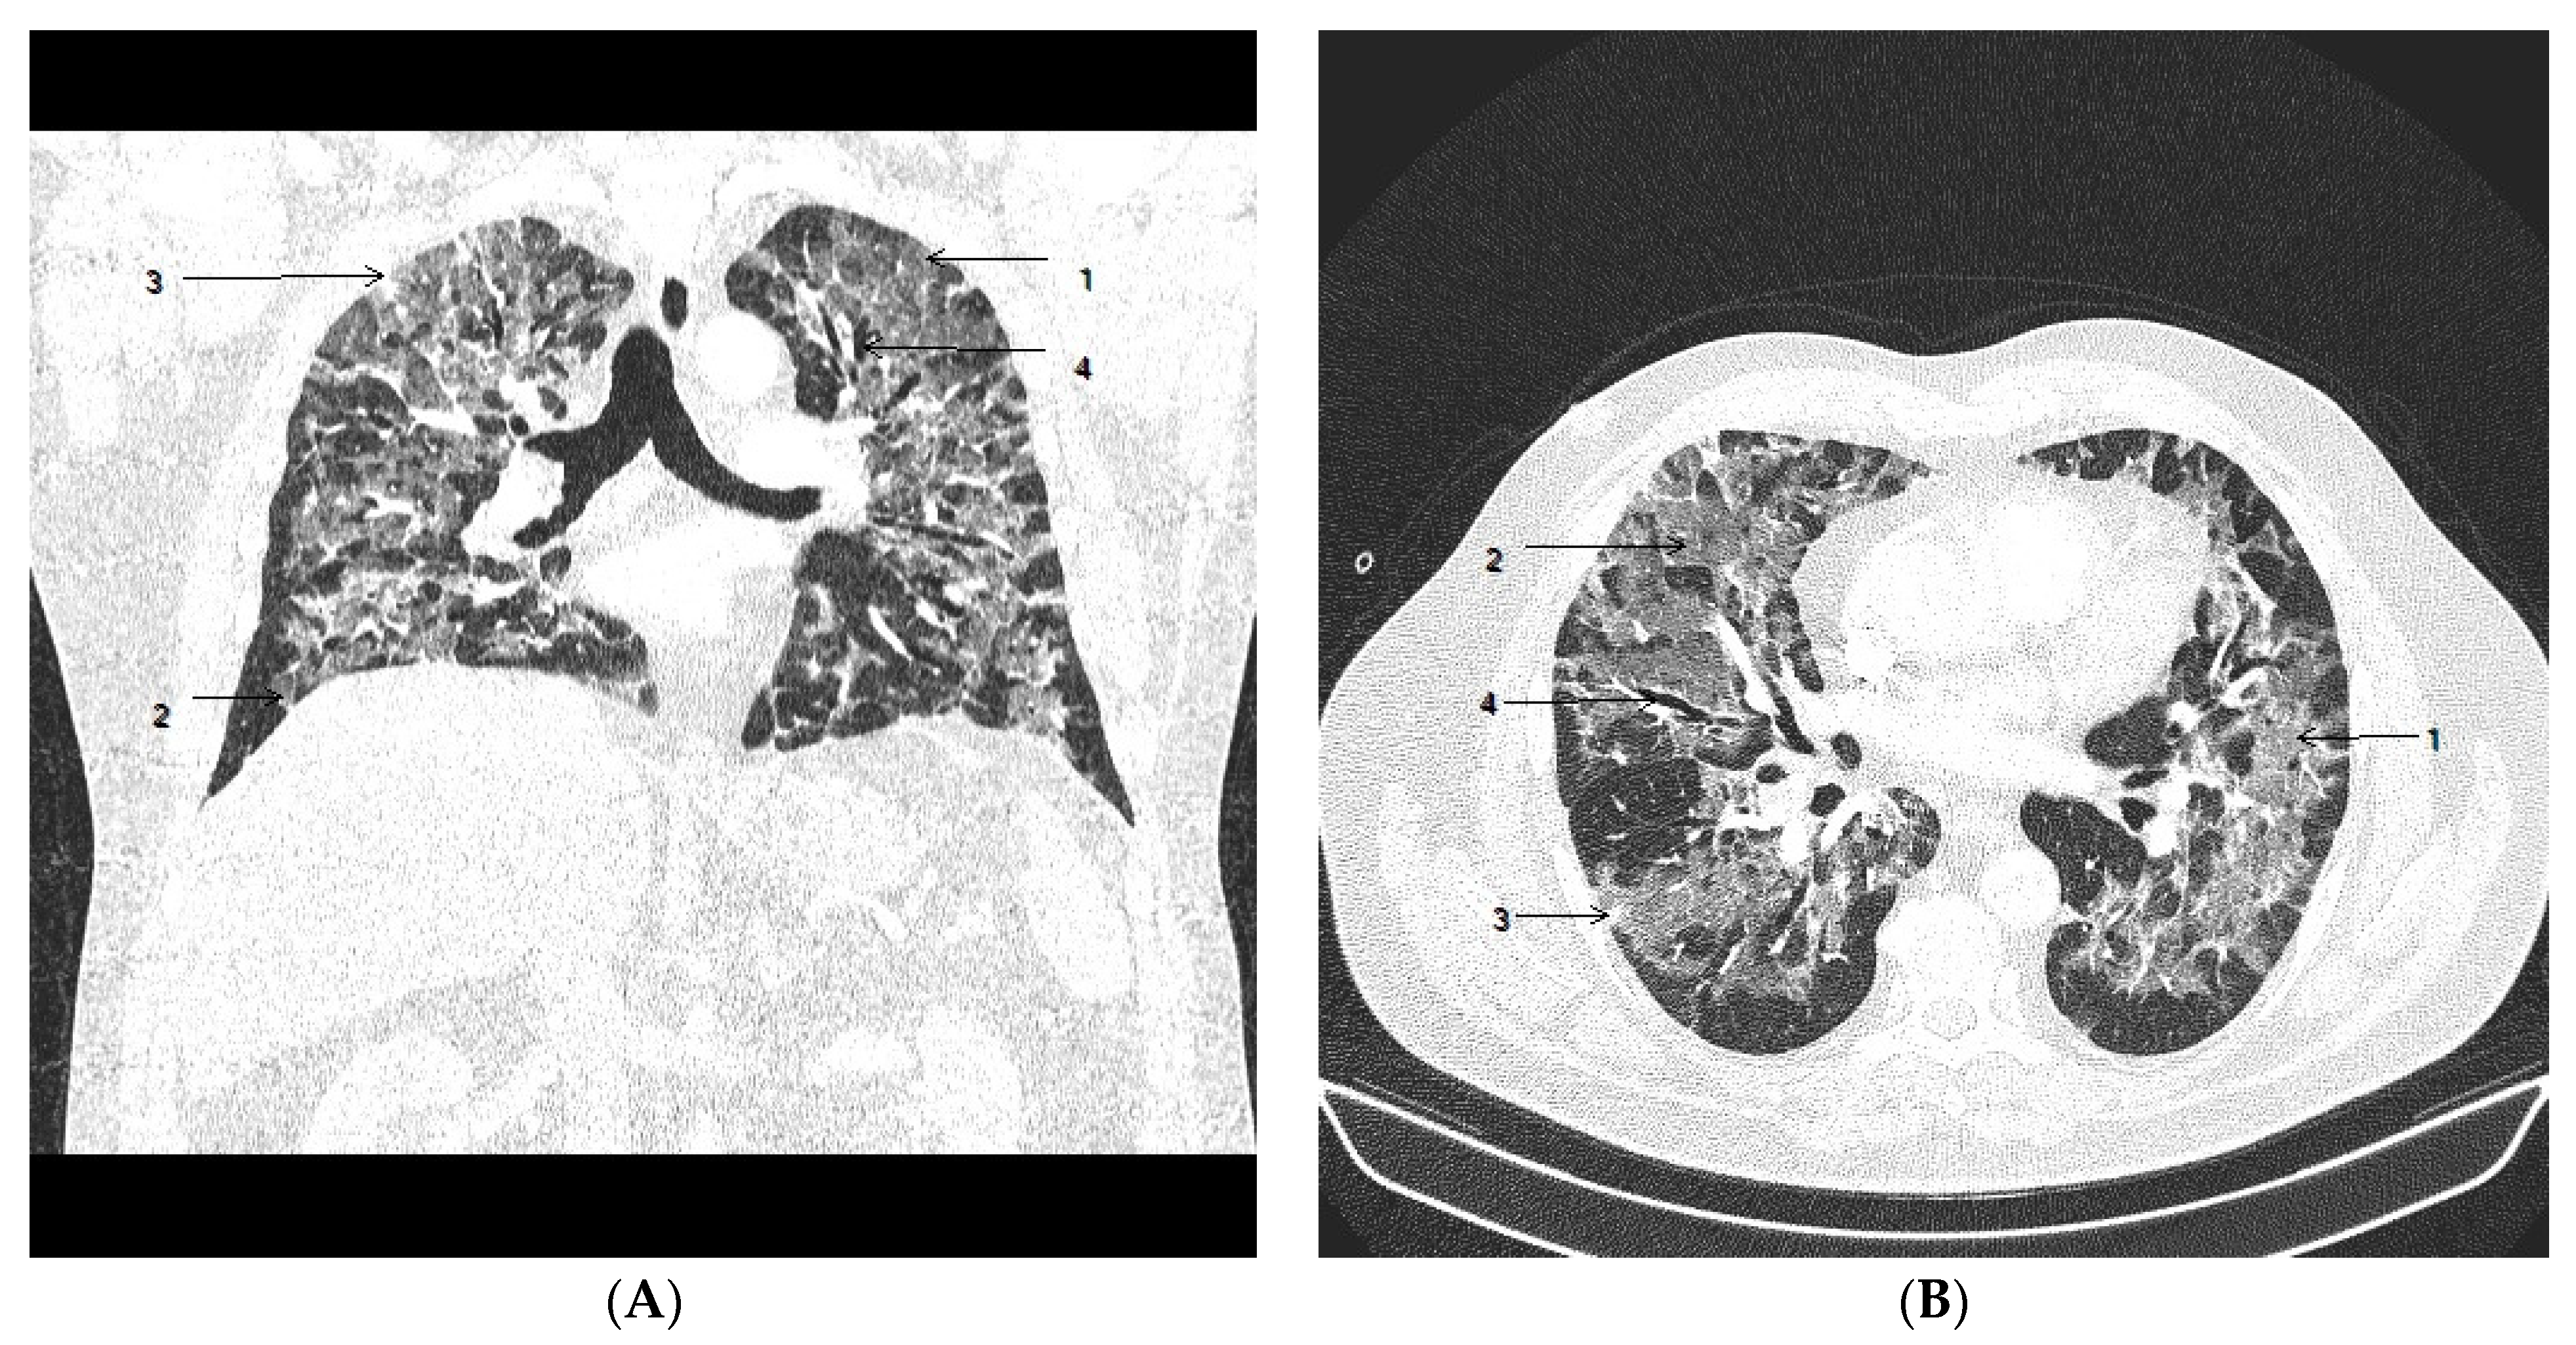

2. Case Presentation

2.1. Clinical Course

2.2. Autopsy Investigation